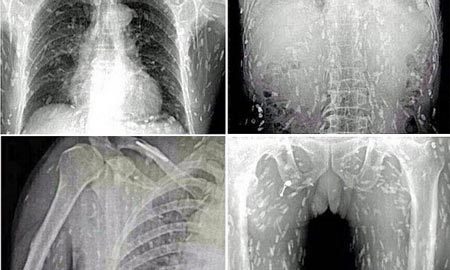

| Các hình ảnh chiếu chụp cho thấy, người đàn ông bị nhiễm sán dây dày đặc toàn thân vì ăn quá nhiều món gỏi nhiễm khuẩn. Ảnh: Daily Mail |

Người đàn ông không được tiết lộ danh tính ở Trung Quốc đã tới thăm khám bác sĩ với các triệu chứng đau dạ dày và ngứa ngáy da. Anh kinh hoàng khi được thông báo, kết quả chiếu chụp hé lộ toàn bộ cơ thể anh đã bị nhiễm sán dây dày đặc sau khi ăn quá nhiều sashimi - gỏi cá hoặc thịt kiểu Nhật.